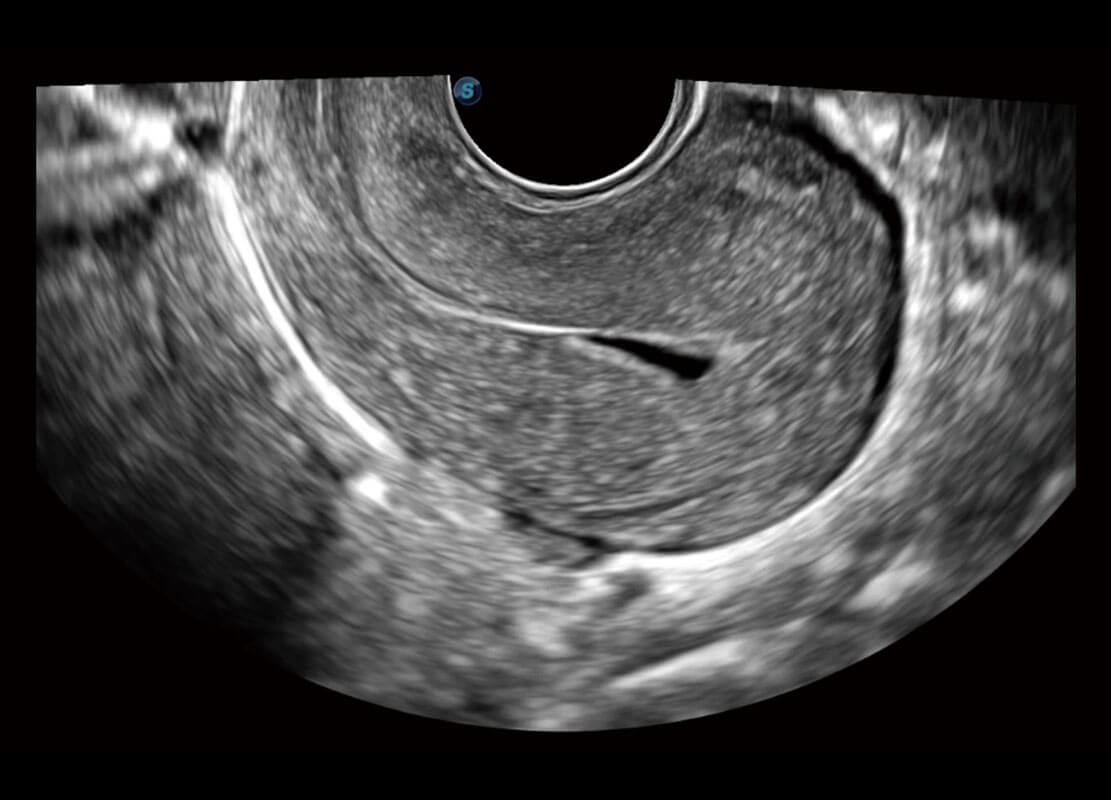

• 腔内三维-宫内节育器

• 腔内三维-光影成像